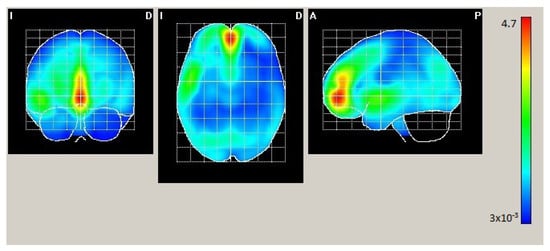

| AAL | X | Y | Z | Act. [µA/m] |

|---|---|---|---|---|

| Frontal_Mid_Orb_L | −2 | 54 | −4 | 2.631 |

| Frontal_Mid_Orb_R | 2 | 54 | −4 | 2.590 |

| Frontal_Sup_Medial_L | −2 | 54 | 0 | 2.586 |

| Cingulum_Ant_L | −2 | 50 | 0 | 2.568 |

| Frontal_Sup_Medial_R | 2 | 50 | 0 | 2.535 |